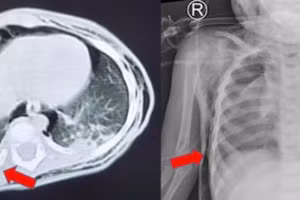

GD&TĐ - Bé gái 3 tuổi sốt cao liên tục, ho nhiều, nhập Bệnh viện Nhi Đồng Thành phố trong tình trạng suy hô hấp nguy kịch được đặt nội khí quản, thở máy.